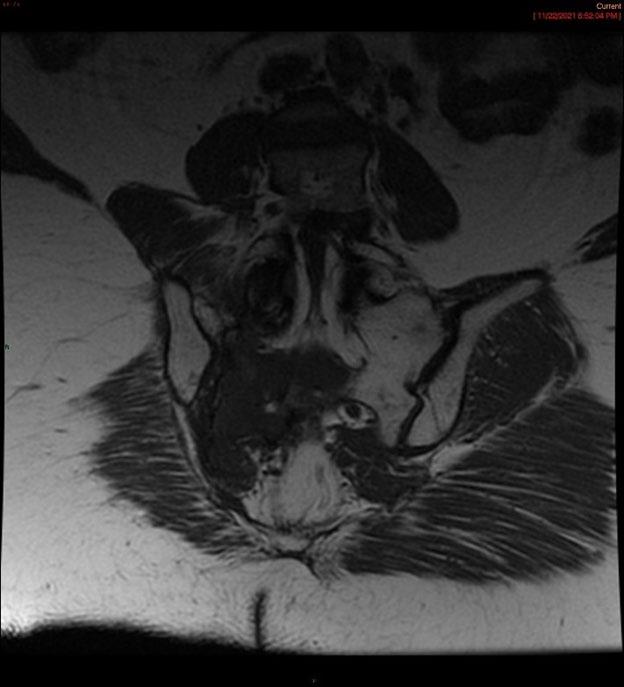

Create a flipbook